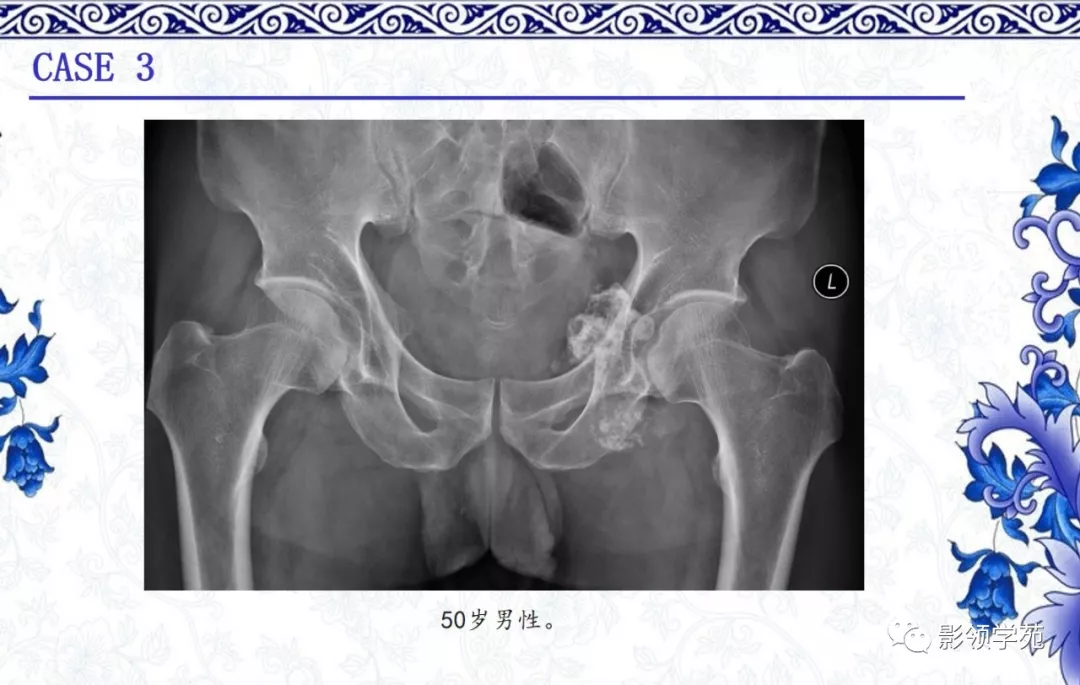

骨软骨瘤

· 良性肿瘤

·多见于30岁以下

·起源于软骨内化骨的骨骼,长骨干骺端多见

·影像表现:

1. 骨表面突起,背向关节,皮质及髓腔与母骨延续

2.软骨帽非矿化部分在磁共振T2WI呈高信号

3.成人软骨帽厚度超过1.5-2cm需怀疑恶变